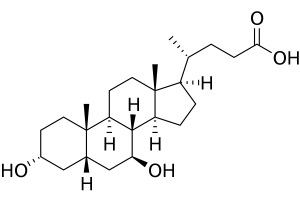

Силімарин та його похідні ще з давніх часів застосовують як гепатопротектори. Гастроентерологи та терапевти широко використовують ці засоби у повсякденній практиці, адже поширення патології печінки в усьому світі набирає обертів.

Мы все хорошо знаем, как сложен и долог путь лекарственного препарата от производства до клиники. Не каждый препарат выдержит проверку экспериментом, временем, а самое главное – практикой.

Желчекаменная болезнь известна многим не понаслышке. По статистике в Украине от камней в желчном пузыре или желчевыводящих протоках страдают от 10 до 15% людей.